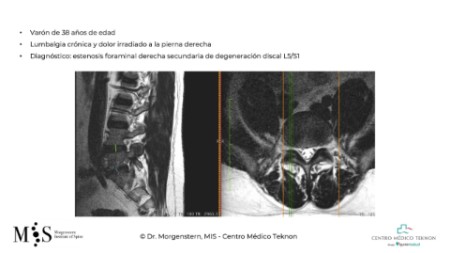

Cas Clínic Abordatge anterior (ALIF) i lateral-oblic (OLIF)

Video de cirurgia anterior i lateral-oblíicua d’una pacient de 53 anys

que només podia caminar amb l’ajut d’un bastó per dolor lumbar

exacerbat. La pacient inicia deambulació sense dolor a les 12 hores

després de la cirurgia amb alta hospitalaria en menys de 48 hores.